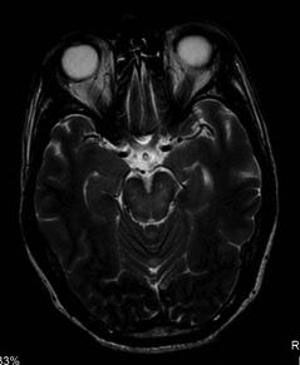

Case History: 27-year-old male with worsening vision in the left eye for five months.